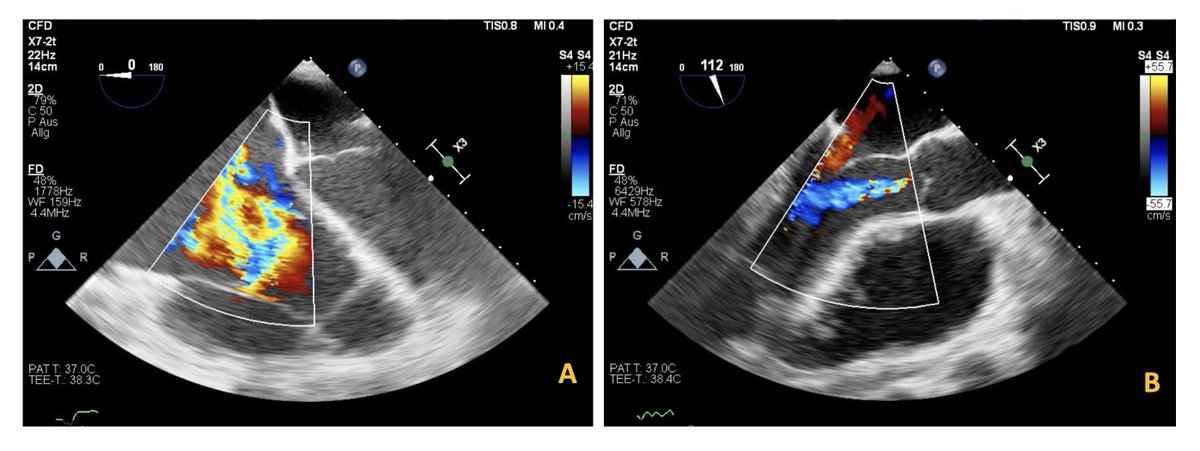

Long-standing, asymptomatic ventricular fibrillation under LVAD support leading to disseminated intracardiac thrombosis Maria Papathanasiou @Morshuis #AHAJournals ahajrnls.org/4jeSy0v